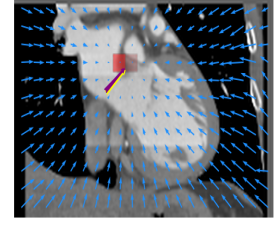

Finally, the proposed network was evaluated for the detection of five additional landmarks: the left coronary ostium, the bifurcation of the LM into the LAD and the LCx, and the origin of the left, non-coronary, and right aortic valve commissures (see Fig. 2). Fig 3 shows vector fields visualizing the predicted displacement vectors in three viewing planes in an image from the test set (for more results, see Appendix). Table 3 lists the Euclidean distance errors between the predicted landmark locations and the reference landmark locations. In addition, box-and-whiskers plots are shown in Fig 4. The best results were obtained for the origin of the right aortic valve commissure. Detection of the origin of the left aortic valve had the most narrow distribution. Outliers were seen during detection of the right ostium, the bifurcation of the LM, and the origin of the non-coronary, and the left aortic valve commissure.

Refer to caption Refer to caption Refer to caption

Figure 3: Vector fields visualizing the predicted displacement vectors in the axial, coronal, and sagittal plane in an image from the test set where detection of the right coronary ostium was performed. The magnitudes of the vectors should point at the right ostium, but they are rescaled for visualization purposes. The red squares indicate posterior probabilities larger than 0.5, obtained by the classification network for image patches. Reference and computed landmark annotations are indicated with a yellow and purple arrow, respectively.